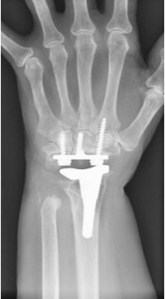

Wrist Arthritis with focus on Wrist Arthroplasty